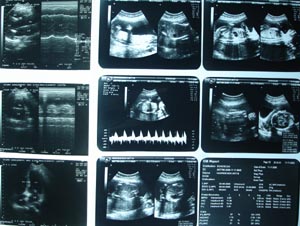

Obstetric Ultrasonography 1

2nd & 3rd trimester USG has its own way of performance. It should include BPD biparital diameter & head circumference (by measuring OFD-occipito Frontal diameter) in addition. Location of placenta with its condition i.e. stages of maturation & position. Foetal abdominal circumference has to be measured at level of adrenal. Vital organs has to be evaluated. Brain & spine has to be given due importance. Amniotic fluid can be assessed by measuring the column of amniotic fluid in all 4 quadrants. Loop of the chord has to be seen. Cosidering all this parameters & confirming about movement of all 4 limbs, & measuring about femur length, gestational period has to be decided. This conclusion has to be matched with LMP (given in h/o) & EDD (expected date of delivery) should be given. Anomaly if present should be discussed with patient or obstetrician & give recommendation.